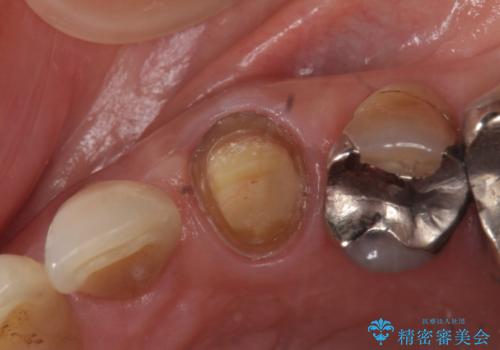

- 他院にて左上3番の被せ物を勧められたが、根管治療からやり直したいと当院にいらっしゃった方の症例です。

再根管治療後、オールセラミッククラウンによる補綴を行いました。